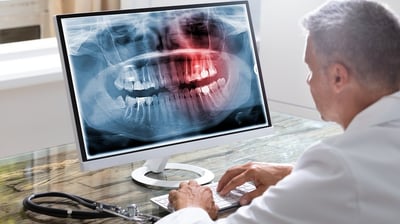

Radiografii dentare digitale

Radiografiile dentare digitale utilizează tehnologie avansată pentru a obține imagini detaliate ale dinților, oaselor maxilare și țesuturilor orale.